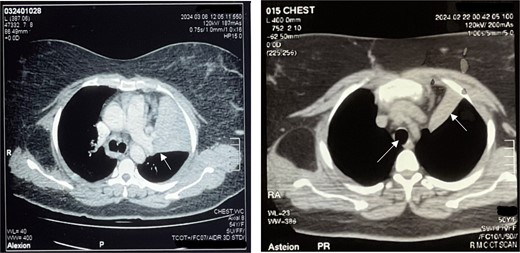

A 50-year-old female, with hypertension and asthma, presented with left shoulder pain and chest heaviness persisting for a month. She denied substance use and had no family history of cardiovascular disease. Initially suspected of coronary syndrome, a negative cardiac workup was conducted at an outside hospital. Chest auscultation revealed normal findings, and a prior CT scan indicated a large fat-density lesion measuring approximately 9.1 × 6.9 × 9.3 mm under the scapula, with consolidative opacities in the left lung lingular segments suggestive of collapse consolidation (Fig. 1).

Left: Right main bronchus shown by black arrowhead and inflamed lung parenchyma shown by arrowhead. Right: Trachea and collapsed lung on CT scan (white arrowhead).